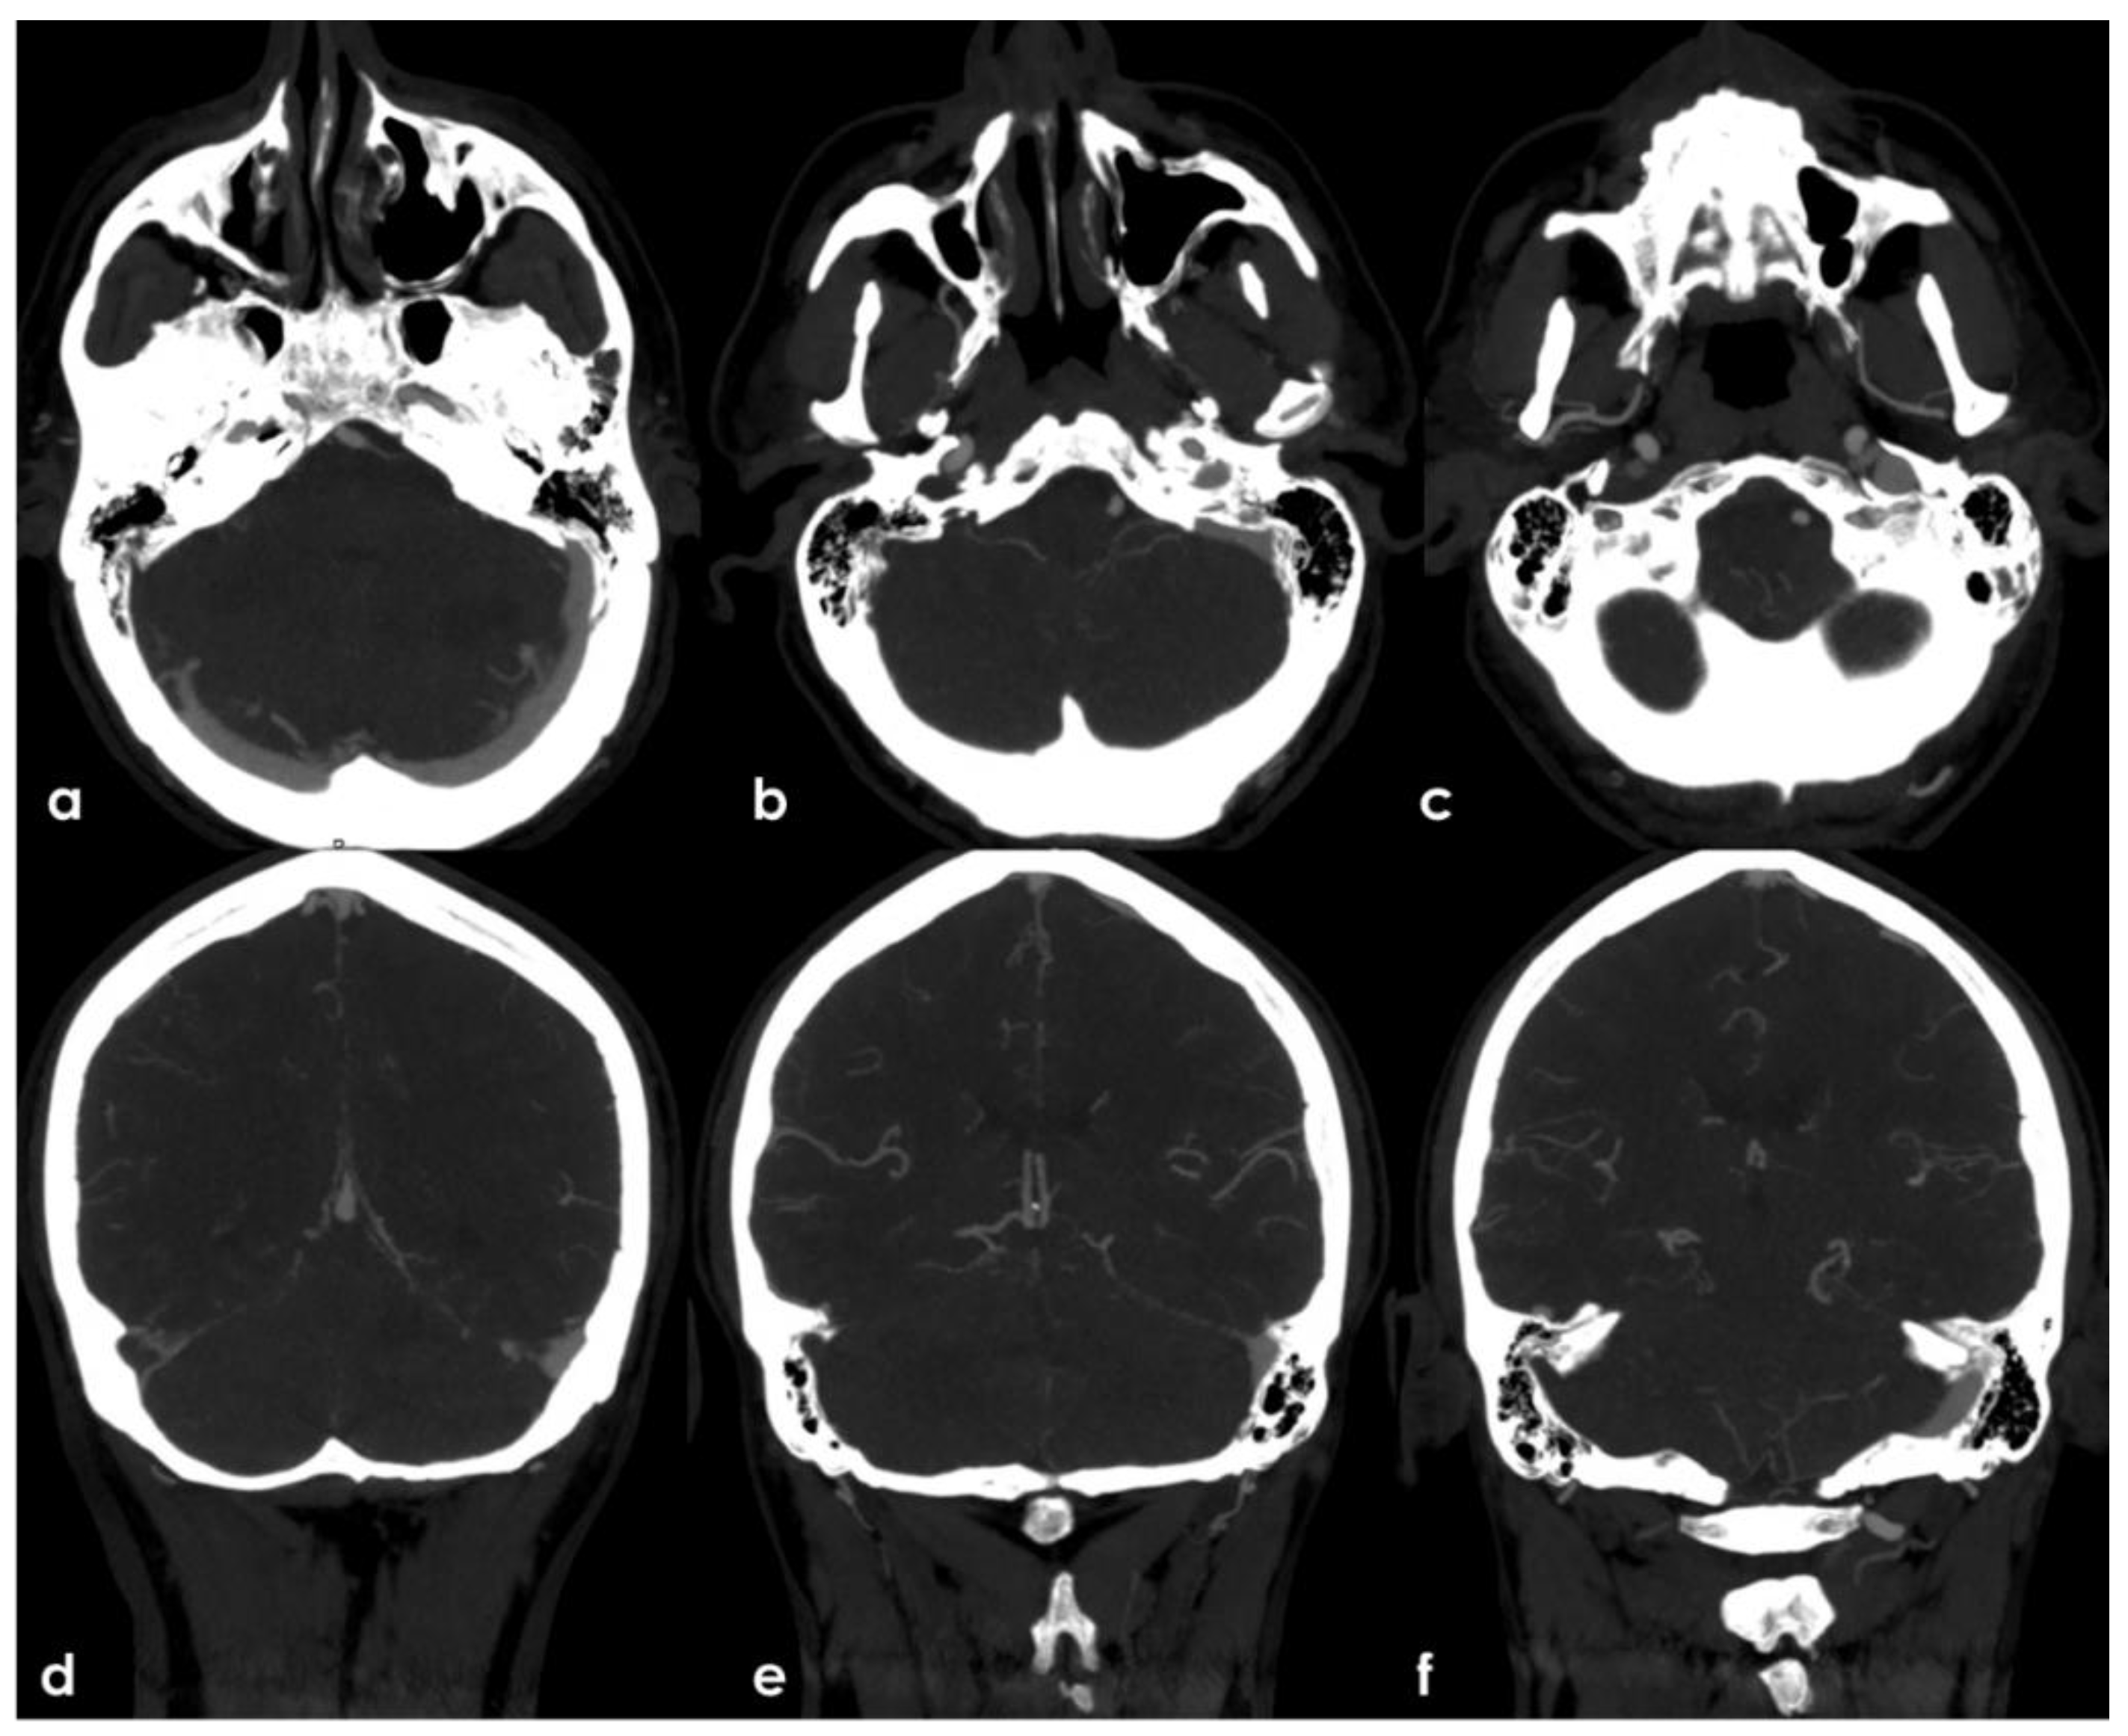

• A lack of contrast filling of the right lateral dural venous system involving transverse sinus (TS) and sigmoid sinus (SS) and also reaching the jugular bulb and the proximal extracranial segment of the right internal jugular vein (IJV).

The intraluminal arterial hypodensities described in (a,b) (Figure 2) are suggestive for intra-arterial partially floating thrombi with V4 VA occlusion (c) (Figure 3), with a presumed mechanism of artery-to artery embolism. Conversely, the filling defect on the intracranial venous compartment (right TS, SS and IJV) (d) (Figure 4) is highly suggestive of cerebral venous thrombosis (CVT).

Figure 4. Arch-to-vertex CTA with MIP reconstructions. The lack of contrast filling of the right TS (from its middle segment), SS and IJV in comparison with the regularly contrast filled contralateral segments is showed in axial cranio-caudal slices (ac) and in coronal posterior-to-anterior slices (df).